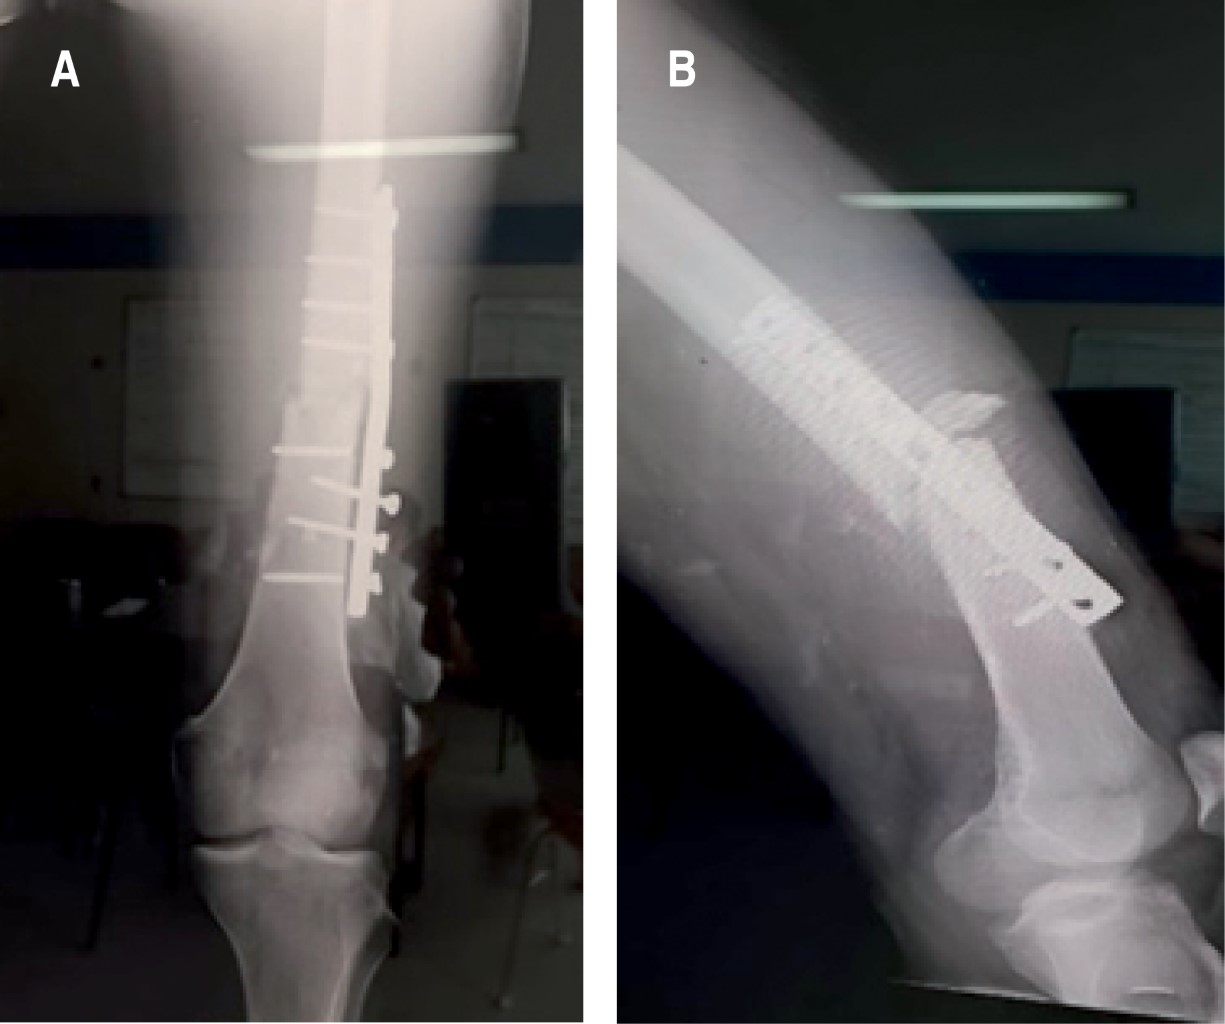

Masculino de 25 años de edad, sin comorbilidades ni antecedentes de importancia para el padecimiento actual; inicia su cuadro tras accidente de tránsito en motocicleta, que le ocasiona una fractura expuesta diafisaria femoral izquierda, tratada mediante aseo quirúrgico y fijación externa; el paciente tiene una evolución tórpida, y a los seis meses se le diagnostica pseudoartrosis aséptica, por lo cual acude a nuestra unidad hospitalaria. A la exploración física observamos miembro pélvico izquierdo con fijador externo sin datos de infección y con heridas quirúrgicas ya cicatrizadas; no realiza marcha y con rangos de movilidad en rodilla ipsilateral, flexión de 90 grados, extensión de menos 5 grados y se observa radiografía sin datos de consolidación ósea (Figura 1).

Masculino de 23 años, sin comorbilidades ni antecedentes de importancia para el padecimiento actual, en el mismo accidente de tránsito en motocicleta, presenta fractura diafisaria de fémur izquierdo que es intervenida quirúrgicamente mediante osteosíntesis con placa DCP (Dynamic Compression Plate) de 4.5 mm, y que de la misma manera, tras seis meses de evolución, presenta ausencia de consolidación ósea, además de fatiga de material de osteosíntesis, por esta razón acude a nuestra unidad hospitalaria (Figura 5). A la exploración lo encontramos con herida quirúrgica cicatrizada adecuadamente, rangos de movilidad en rodilla y cadera completos, pero limitados por dolor.

Figura 1

Figura 5